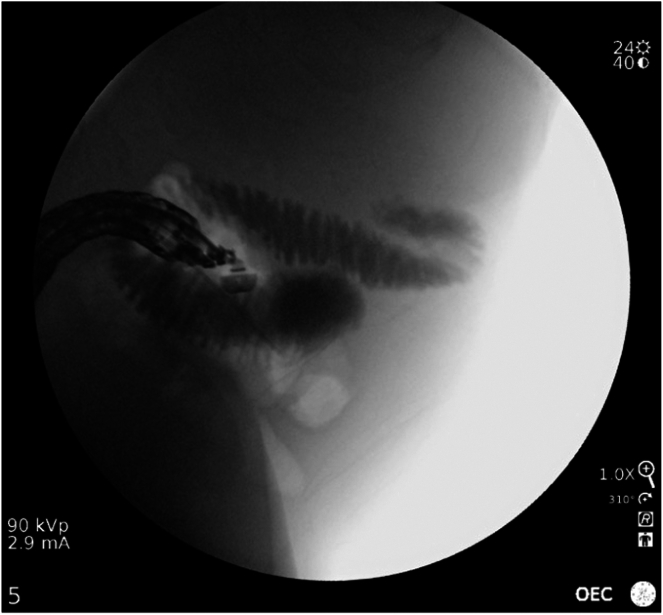

Malignant bowel obstruction is a challenging complication in advanced gastrointestinal malignancies with varying treatment strategies including medical, surgical and endoscopic therapies, each with their own limitations. Endoscopic ultrasound–guided enterocolostomy has been previously reported as an option for patients who are not surgical candidates or ideal candidates for enteral stenting. In this case, endoscopic ultrasound–guided enterocolostomy is used for the palliation in a patient with a completely obstructing large cecal adenocarcinoma who declined surgical intervention.